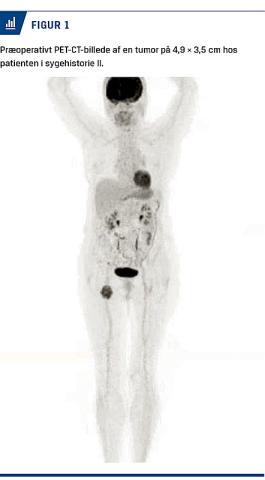

Knuden blev beskrevet som »subkutan, ca. 5 cm, glat, blød, adhærent i dybden men forskydelig«. Trods tidligere melanomdiagnose blev hun først udredt for sarkom. En MR-skanning viste patologisk lymfeknude i højre lyske. En initial finnålsbiopsi var uspecifik, men med BRAF-mutation. Ved to efterfølgende grovnålsbiopsier bekræftedes diagnosen melanommetastase. PET-CT viste en tumor på 4,9 × 3,5 cm i højre lyske og øget aktivitet foran højre iliacakar (Figur 1). Patienten blev henvist i pakkeforløb til en plastikkirurgisk afdeling, hvor der blev foretaget radikal lymfeknuderømning i ingvinal- og iliacagebetet. Der var melanommetastaser med perinodal vækst ud i fedtvæv i to af otte ingvinale lymfeknuder og i en af ni iliakale lymfeknuder.